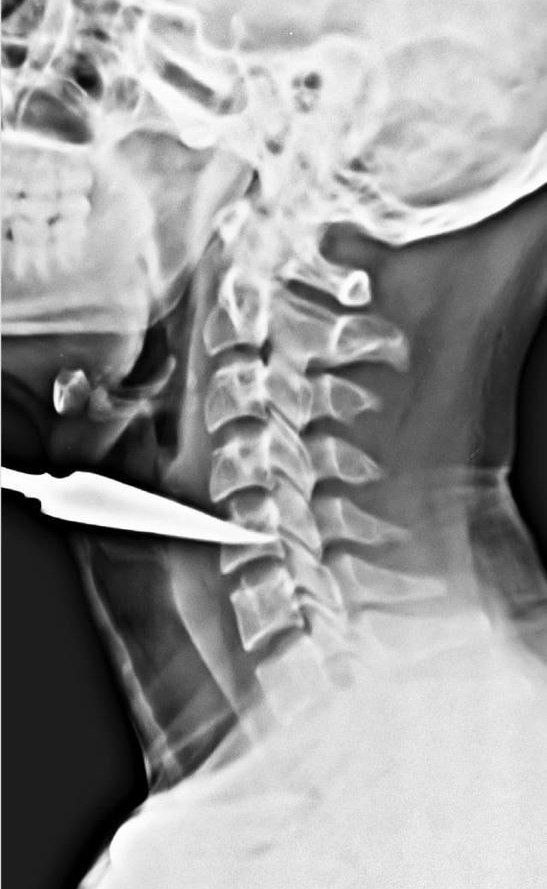

તીર ગરદનમાં સી - 5 વર્ટીબ્રા સુધી પહોંચ્યું

30, મે ના રોજ સાંજના 5 વાગ્યાના આરસામાં મધ્યપ્રદેશના અલીરાજપુરના આંબવા ગામે તીર વાગવાની એક ઘટના બની હતી. જેમાં 25 વર્ષિય યુવકના ગળાના ભાગે તીર ઘૂસી જતા તે ગંભીર રીતે ઘવાયો હતો. ગંભીર ઇજાગ્રસ્ત યુવકને તાત્કાલિક સારવાર અર્થે દાહોદની ખાનગી હોસ્પિટલમાં લઇ જવામાં આવ્યો હતો. જ્યાં તેની ટૂંકી સારવાર બાદ તેને વધુ સારવાર અર્થે એસએસજી હોસ્પિટલમાં રીફર કરવામાં આવ્યો હતો. 31, મે ના રોજ વહેલી સવારે યુવકને એસએસજી હોસ્પિટલમાં લાવવામાં આવ્યો હતો. તેને એસએસજી હોસ્પિટલના ઇએન્ડટી અને હેડ નેક સર્જકી ડિપાર્ટમેન્ટમાં દાખલ કરવામાં આવ્યો હતો. જ્યાં રેડિયોલોજીસ્ટ દ્વારા તેની તપાસ કરતા સામે આવ્યું કે, તીર ગરદનમાં સી - 5 વર્ટીબ્રા સુધી પહોંચ્યું છે. સદ્ભાગ્યે ગરદનની મુખ્ય રક્તવાહિનીઓ તથા નસ તેની ઇજાથી સલામત છે.

જેથી એસએસજી હોસ્પિટલના ઇ એન્ડ ટી વિભાગ અને ન્યુરો સાયન્સ વિભાગ દ્વારા સંયુક્ત રીતે યુવકનું ઓપરેશન કરવામાં આવ્યું હતું. તેનું ગળાનું ક્રિટીકલ ઓપરેશન કરીને તીરને બહાર કાઢવામાં આવ્યું હતું. દરમિયાન તીરના કારણે થાઇરોઇડ કોમલાસ્થિ (એર વે) અને ફૂડ પાઇપ વિંધાઇ ગઇ હોવાનું જણાઇ આવ્યું હતું. હાલ નિષ્ણાંત તબિબો દ્વારા 14 ઇંચના તીરને બહાર કાઢી લેવામાં આવ્યું છે. અને હાલ દર્દીની હાલત સ્થિર હોવાનું હોસ્પિટલ સુત્રો જણાવી રહ્યા છે.